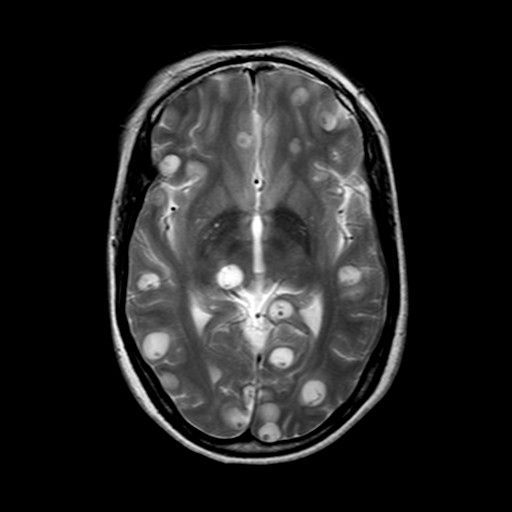

Neurocysticercosis refers to parasitic infection of the brain. The parasite involved is taenia solium. The parasites are present in the larval cysts. Neurocysticercosis is a common cause of seizures. It is the leading causes of adult onset generalized epilepsy. The risk of neurocysticercosis can be minimized by preventing ingestion of raw pig and following proper hygiene. Reference: https://www.cdc.gov/parasites/resources/pdf/npis_in_us_neurocysticercosis.pdf Image via: https://www.cancertherapyadvisor.com/home/decision-support-in-medicine/pediatrics/cysticercosis/